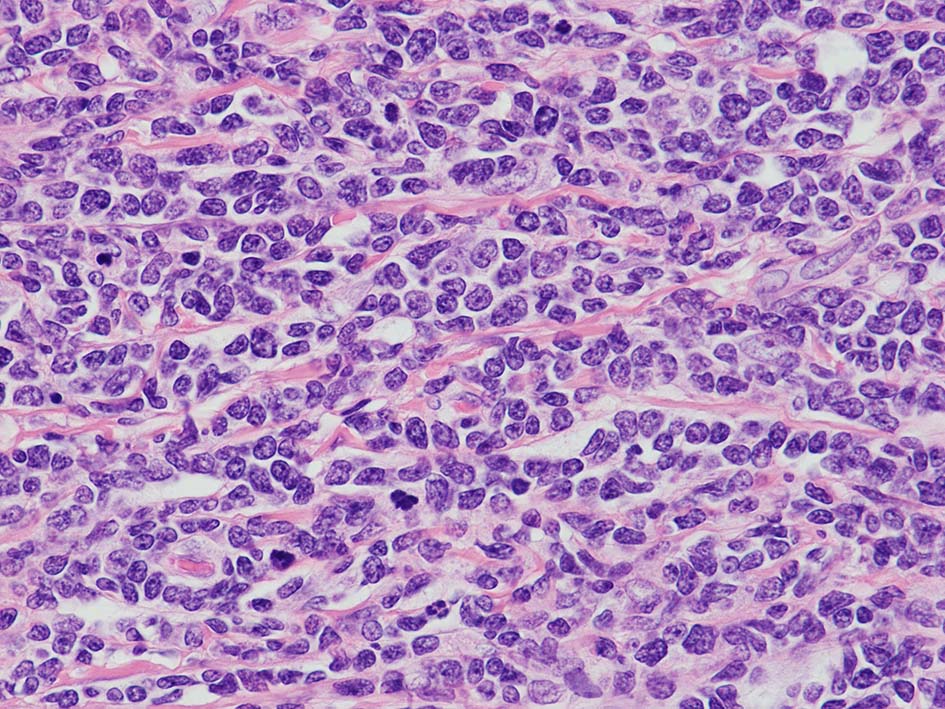

loupe像Aの領域: 精細管をスペアするように, 小型リンパ球優位, 一部中型のlymphoid cellsがシート状密に浸潤増殖する. tubulesのほとんどにはlymphoid cellsが浸潤していないが, LELに似たようなlympho-tubular lesionが少数認められた. x400高倍率では, 増殖細胞は, 粗く, 凝集したクロマチンをもつ類円形, non-cleavedな核をもつ細胞質の乏しいlymphoid cellsである. 核小体か凝集したクロマチンかわかりにくい.

白膜には密に腫瘍性リンパ球が浸潤増殖し, 肥厚, 一部は上図loupe像のように, 腫瘤を形成している. 浸潤リンパ球は精巣実質内よりも, やや大きく, 多稜形, くびれのある核をもち, クロマチンは淡明で核小体が明瞭になってきている.